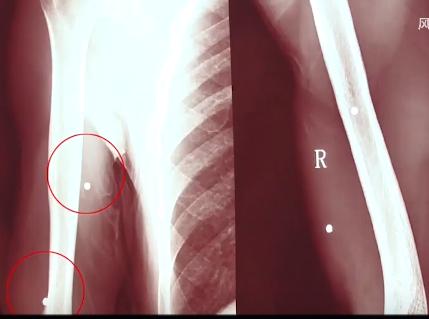

经过验伤,警方判断 这些伤口是用*弹霰**枪打出来的,虽然这种*弹霰**枪是土制的,用的也不是真的*弹子**,但威力依然很大。

因为发射出去的小弹丸很多,所以伤口也多,遍及全身。

医院给任辉取出来了一些,但有些因为太深,已经无法取出来,只能留在体内。

这次受伤,也是极其严重的,取不出的弹丸成了永久的后遗症,之后很长一段时间,任辉应该都不能正常走路了。